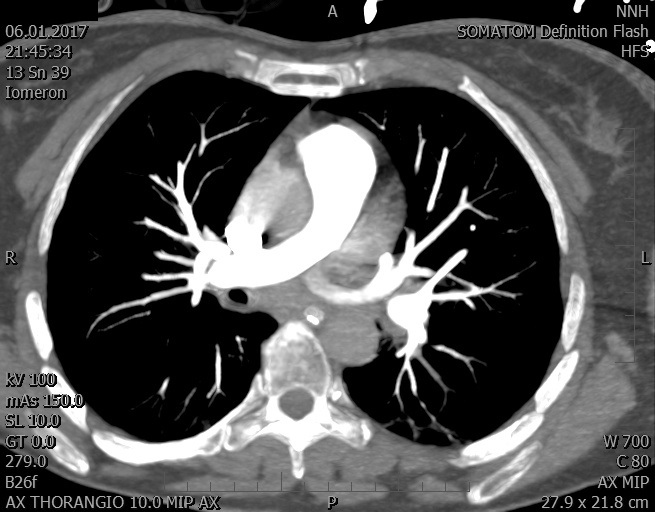

Video 2 - Echokardiograficky byla zjištěna těžká dysfunkce dilatační levé komory s nezvětšenou pravou komorou.Pro nejasnou příčinu zástavy jsme provedli i vyšetření výpočetní tomografií (CT), které vyloučilo plicní embolizaci (série 1 - soubory na konci článku). V den přijetí při přetrvávající oběhové nestabilitě byla nemocná opakovaně defibrilována pro fibrilaci komor se stabilizací rytmu po podání amiodaronu a mesocainu. Dle hemodynamických měření se jednalo o těžký kombinovaný šok. Vstupní laboratorní vyšetření bylo bez větších pozoruhodností. Posléze jsme doplnili anamnézu od příbuzných a zjistili, že pacientka užila do dvou hodin před srdeční zástavou první tabletu amoxicilinu na lehký respirační infekt. Při nevýtěžnosti vstupních vyšetření a nových anamnestických informacích jsme doplnili 14 hodin po kolapsu vyšetření koncentrace tryptázy v séru, která byla extrémně zvýšena (tabulka 2), což nás vedlo k podezření na anafylaxi.